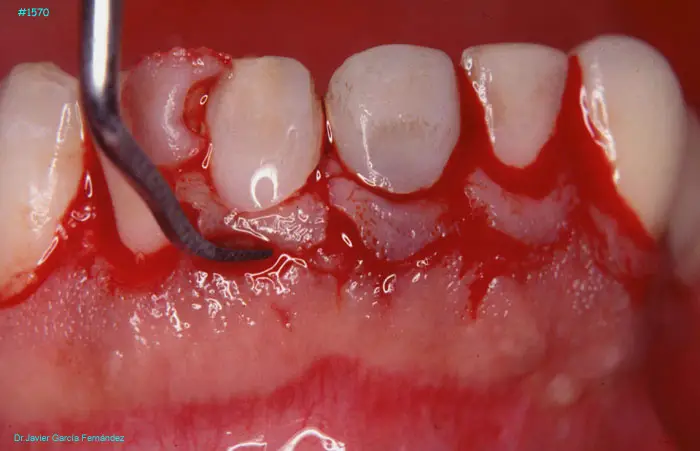

Atlas of Surgical Techniques in Periodontics. Chapter IV. Atlas de Técnicas Quirúrgica en Periodoncia

image 095